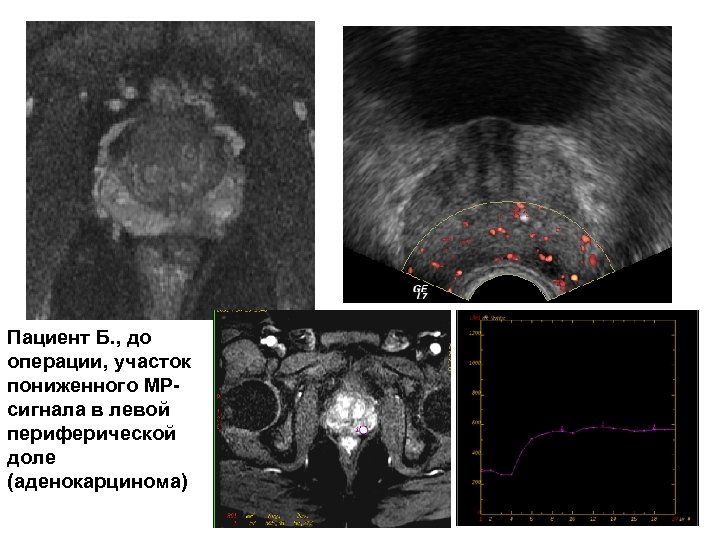

Пациент Б. , до операции, участок пониженного МРсигнала в левой периферической доле (аденокарцинома)